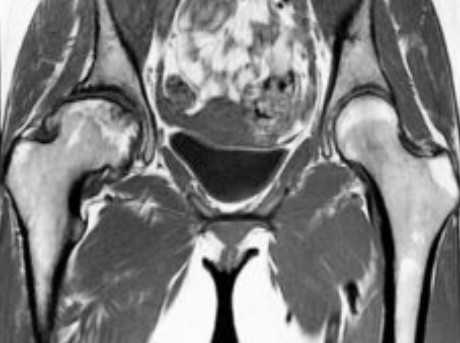

МРТ-признаки остеомиелита лонных костей: расширение сочленения и скопление жидкости с формированием параартикулярных затеков (длинные стрелки), разрастание грануляционной ткани (короткие стрелки), Т2-ВИ, аксиальная (а) и коронарная (в) плоскости